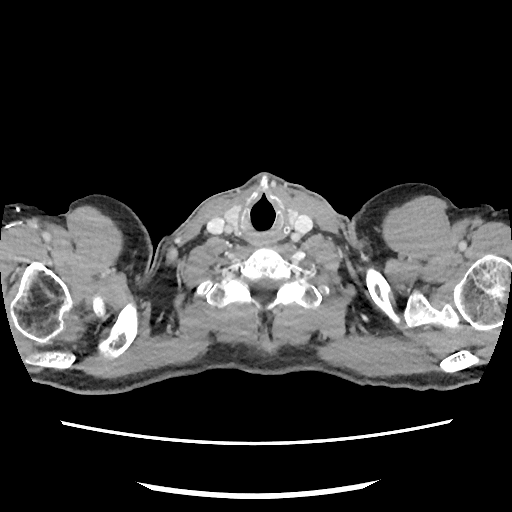

Trots als ik ben kan ik weer de binnenkant van mijn lichaam delen. Opnieuw zonder knobbels en bobbels, gewoon een super gezond lichaam van een jonge 50er.

Hierbij dus weer een mooi inzicht in mijn lichaam, ik ben er blij mee!

Zo knap dat de artsen op deze films kunnen zien of er iets mis is..

Voor mij is het een Onderwater opname